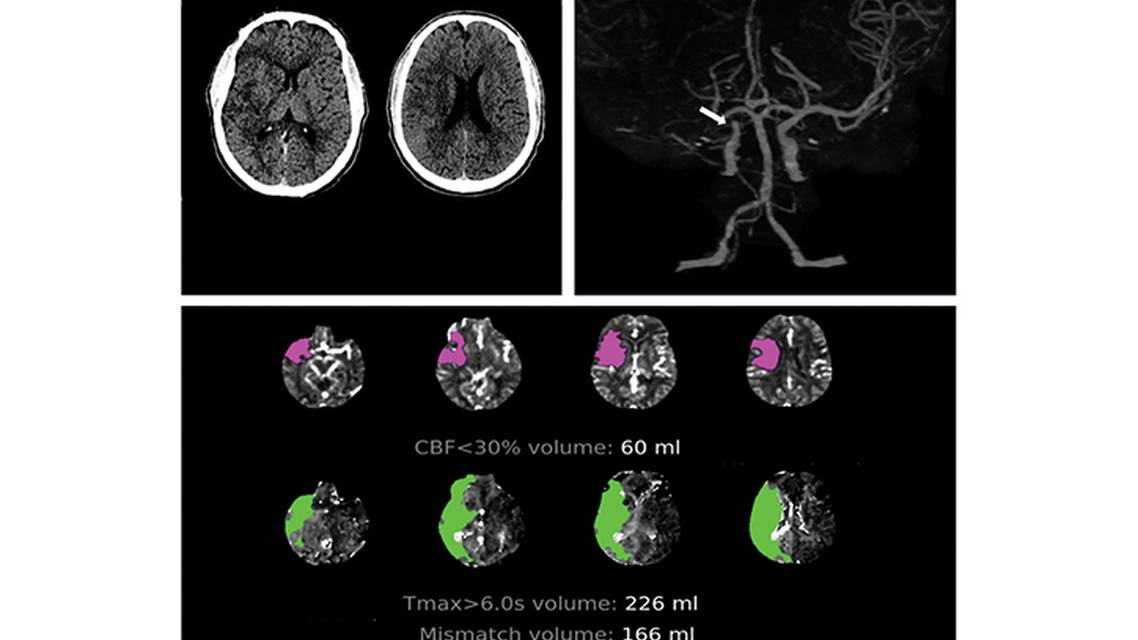

The notion that EVT is futile for people with LVO and substantial volume of irreversible tissue damage (eg, large core strokes; Figure) is based on an anticipated high risk of hemorrhagic transformation and poor functional outcomes despite treatment. Recent studies have delved deeper into the role of EVT in this population. ANGEL-ASPECT (Study of Endovascular Therapy in Acute Anterior Circulation Large Vessel Occlusive Patients With a Large Infarct Core, NCT04551664),3 published in 2023, investigated the safety and efficacy of medical management (MM) plus EVT vs MM alone in cases of anterior circulation LVO with a low ASPECTS (3 to 5). This trial, conducted in China with 456 participants, revealed better 90-day functional outcomes in people treated with EVT (odds ratio [OR], 1.37; 95% CI, 1.11–1.69). The occurrence of symptomatic intracranial hemorrhage (sICH) was significantly higher in the EVT group (6.1%) compared with the MM group (2.7%). Mortality rates were high but similar between the 2 treatment groups (21.7% in the EVT group and 20% in the MM group).

![Figure. Large core stroke. CT shows loss of gray–white matter differentiation in the territory of the right middle cerebral artery with an estimated Alberta Stroke Program Early CT Score (ASPECTS) of 4 (A). CT angiogram shows right internal carotid artery occlusion (arrow) (B). CT perfusion with RAPID automated software (iSchemaView) shows 60 mL volume of infarct core (cerebral blood flow [CBF] <30%) and 226 mL volume of critically hypoperfused tissue (Tmax >6 seconds) (C).](https://cdn.practicalneurology.com/cache/30/2e/302e4d5f0e5ca156f3a71d5b8266fd6d.png)